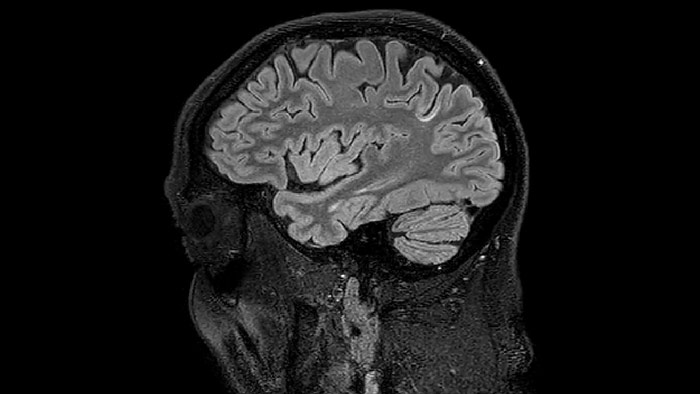

He says the accelerated scanning is achieved via the use of Compressed SENSE and MultiBand SENSE. “We can use Compressed SENSE acceleration factors of about 10 on a 3D FLAIR for instance, which is quite remarkable compared with what we saw with the Achieva. With 3D FLAIR, we can push the spatial resolution to 0.3 cubic mm and it works. Previously, our 3D FLAIR scans lasted about 8 minutes, but now with Elition they are five minutes. The SNR is also visibly better. Our SWI and QSM scans look fantastic. Also, since a lot of neuroimaging is EPI based, using the MultiBand SENSE technique can increase temporal resolution and make it possible to run complicated DTI scans relatively quickly.”

Sagittal 3D FLAIR with 0.3 mm3 voxel volume acquired in 5:12 min. using Compressed SENSE showing a (juxta)cortical MS lesion.